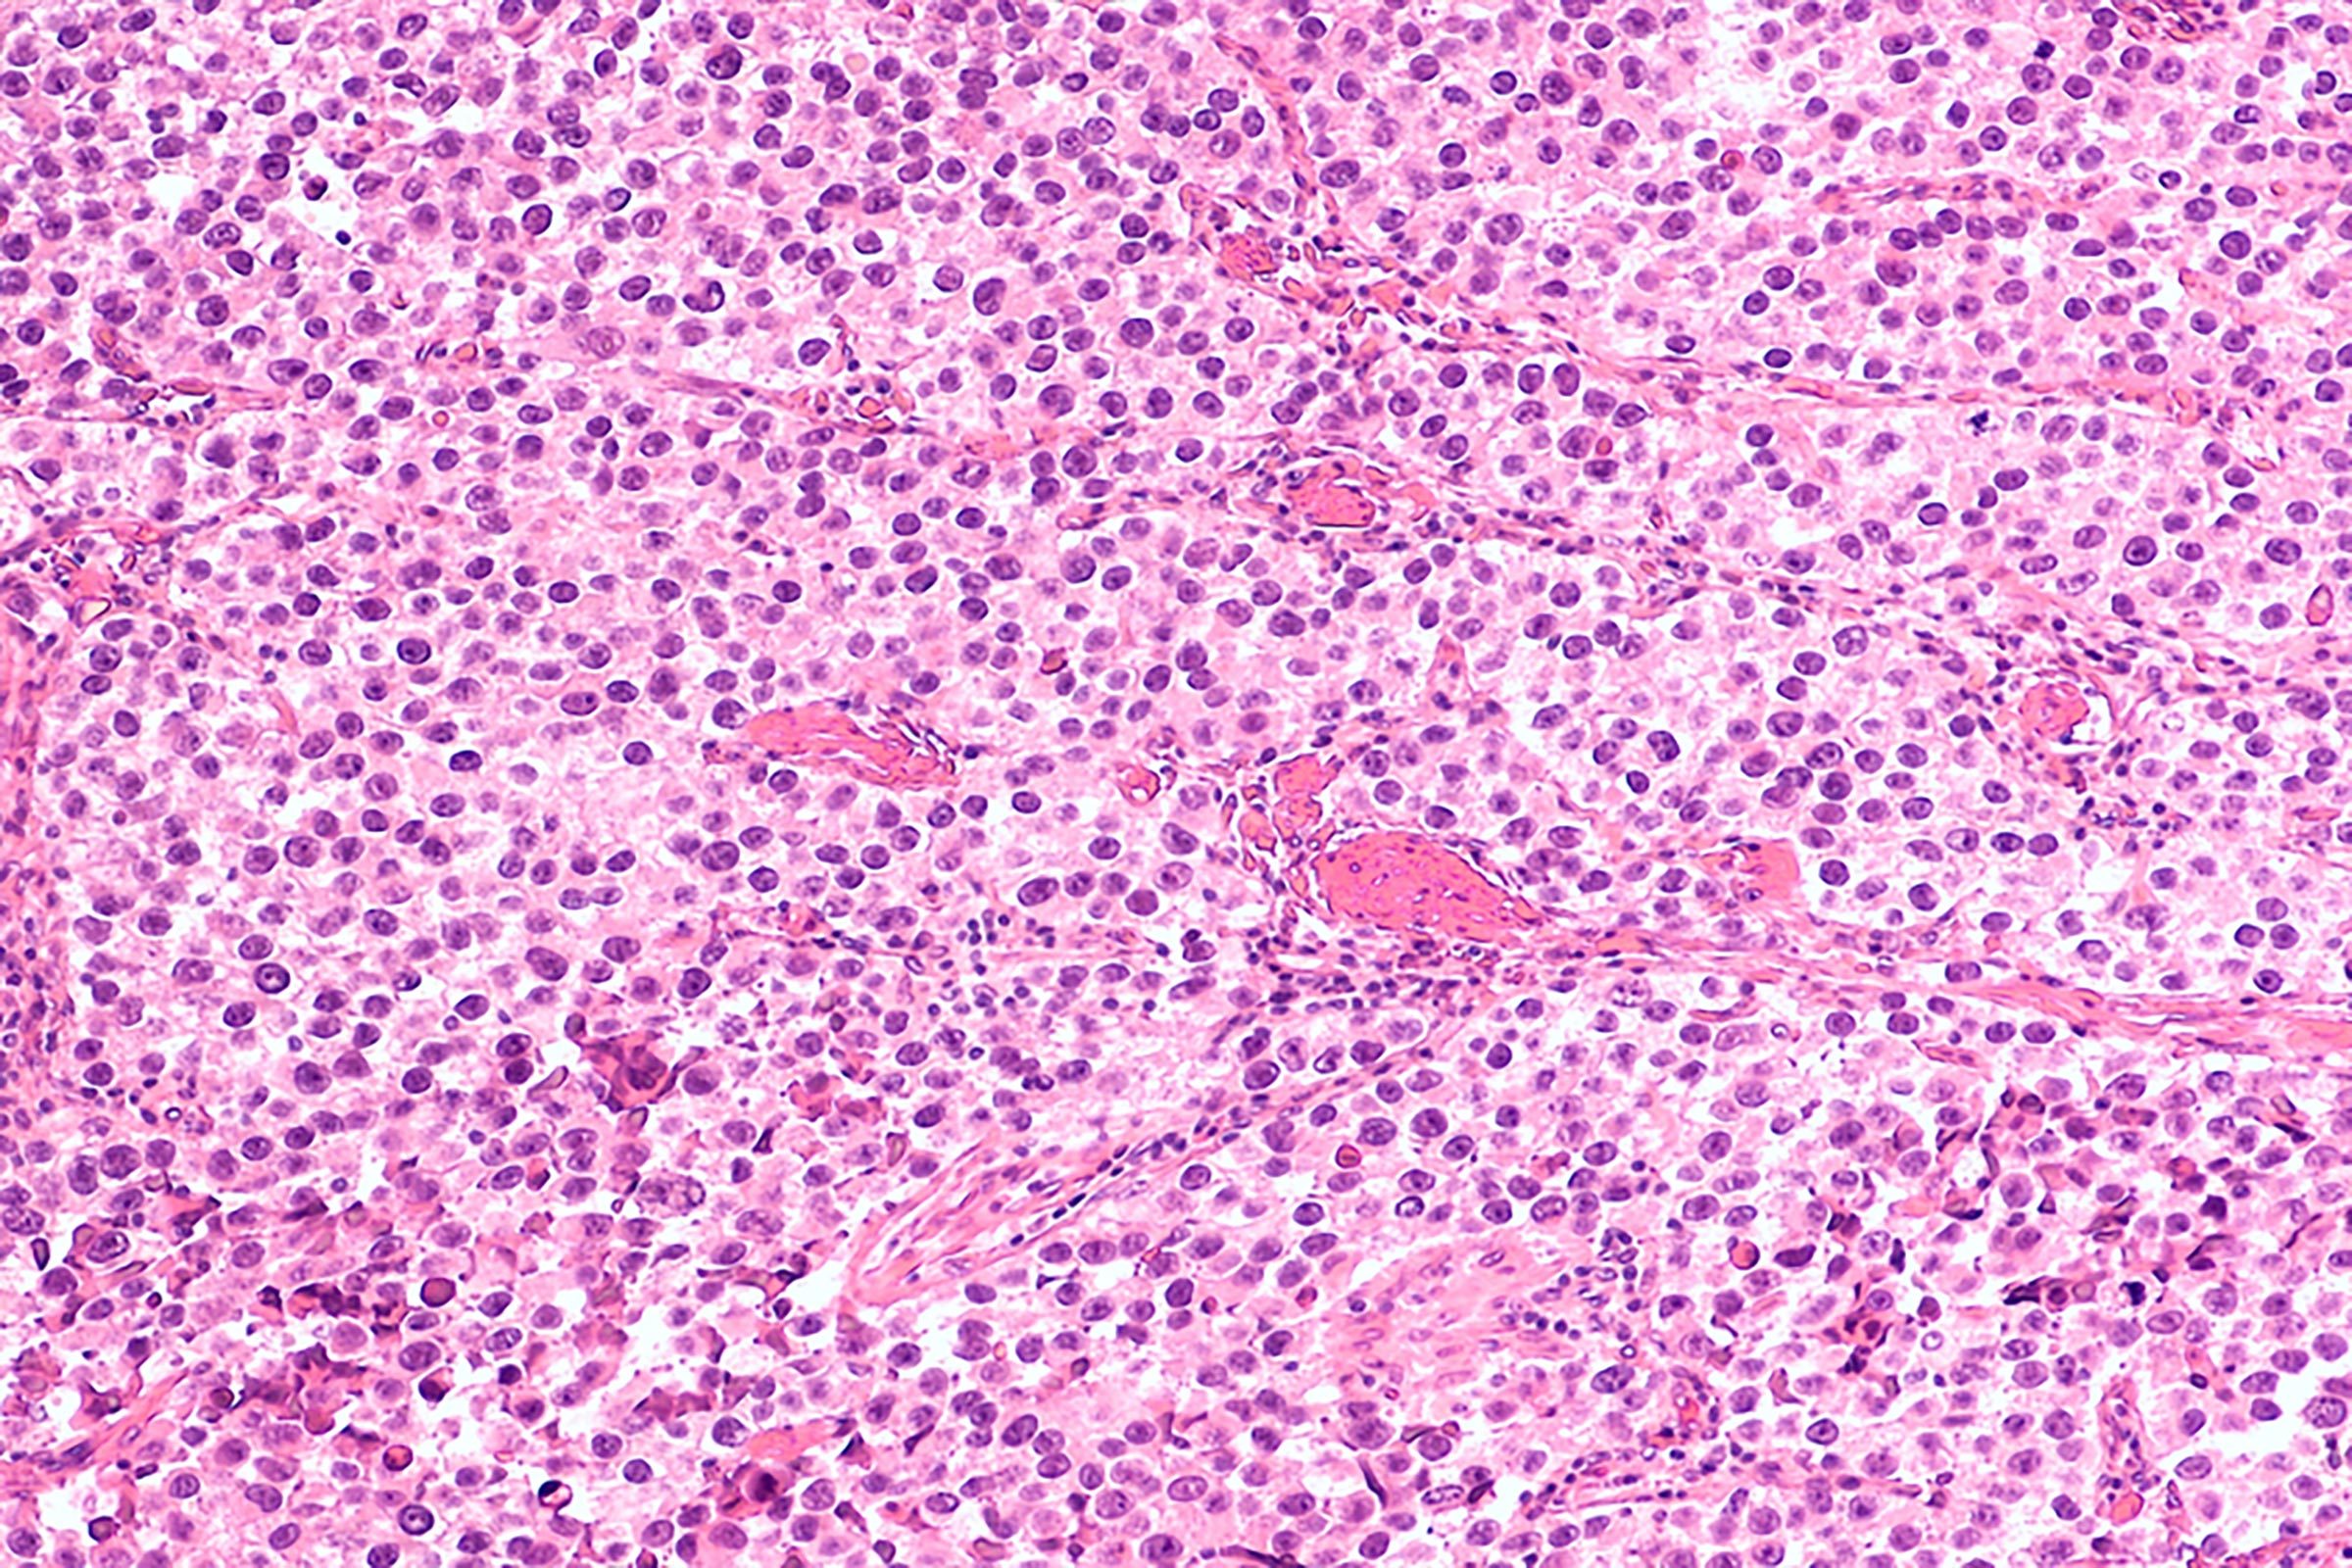

cancercell

Heiti Paves/Shutterstock

Prostate cancer

Prostate cancer seems to run in some families, Dr. Brahmbhatt says. Talking to family members about their health and medical history can help determine your risk and develop an early detection and prevention strategy. “Even though you are under 35, if your dad has prostate cancer, you should get screened earlier than men without a family history.” This can save your sex life too. “If you catch prostate cancer early, there are nerve-sparing surgical approaches that can be done which help retain sexual function, but if you wait too long than the likelihood of sexual side effects are higher.” Next, read about how having sex may slow down aging.